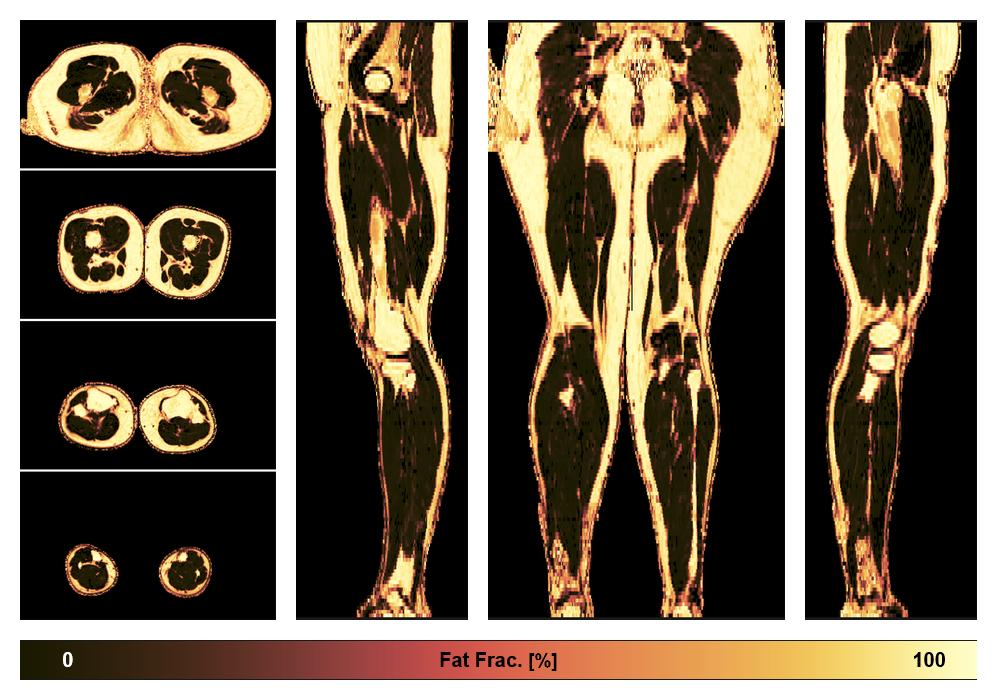

• Fat fraction

The fat fraction of the lower extremity obtained from the dixon reconstruction for muscle water fat quantification.